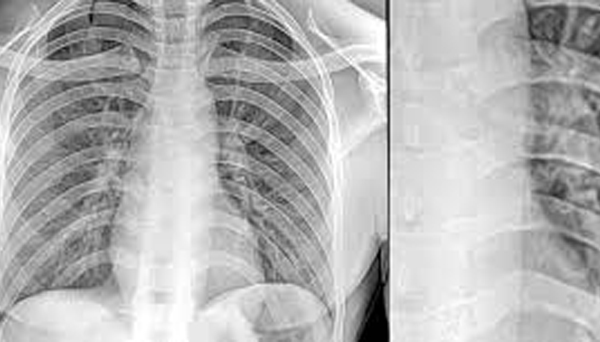

Digital X-Ray is a modern imaging technique that uses digital sensors to capture detailed images of the body’s internal structures, such as bones, organs, and tissues. Unlike traditional X-rays that use film, digital X-rays produce images that can be instantly viewed, enhanced, and stored electronically.

They are widely used for diagnosing fractures, infections, tumors, and other medical conditions. Digital X-rays offer superior image quality, faster results, and lower radiation exposure compared to traditional X-rays.